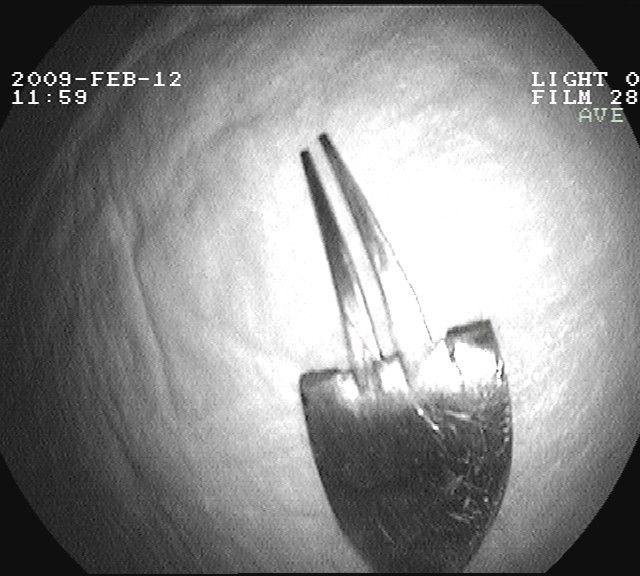

Gastroskopie - verschluckte Gabel im Magen